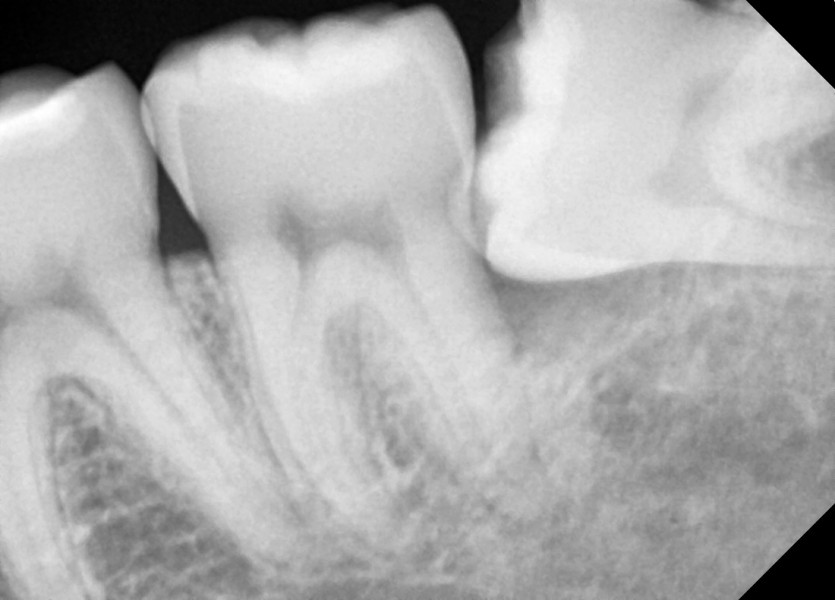

#28,38 사랑니 발치

구강 외과 전문의가 당일 발치했습니다.